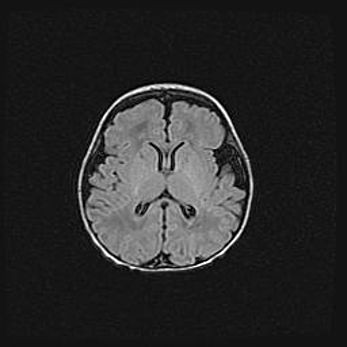

Церебральная ишемия II.

Возраст: 5 дней

Вес: 3400 г

Пол: женский

Окружность головы: 35 см

Срок гестации: 39 недель

Церебральная ишемия – это заболевание, характеризующееся недостаточностью (гипоксией) либо полным прекращением (аноксией) снабжения мозга кислородом по причине закупорки одного или нескольких сосудов. Это приводит к  что метаболическим расстройствам различной степени тяжести в тканях головного мозга, развитию коагуляционных некрозов и гибели нейронов.